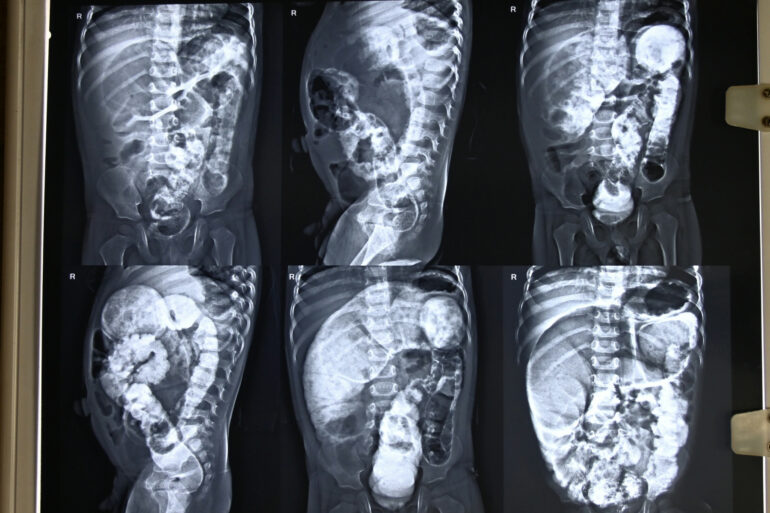

Let us share another paediatric case. Hirschsprung’s Disease is the most common cause of lower intestinal obstruction in neonates. Hirschsprung’s Disease, also known as aganglionic megacolon, ... read more

Let me share another case of congenital/Developmental anomaly, Hirschsprung’s Disease The patient is from the Unnao district. The patient was facing trouble with constipation, which was very painful. ... read more